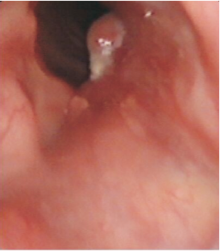

高惠冰:2014年3月患者出现吞咽困难、左耳刺痛、喉部异物感。来院查体: PS评分1分, 颈部见气管造瘘口, 造瘘口右上方可触及肿物。大小约4 cm× 3 cm, 质韧, 活动度差, 无压痛。

2014-03-26喉增强MRI:喉部术后改变, 喉腔内见巨大软组织肿块影, 大小约41 mm× 29 mm, 信号均匀, 边界不清, 增强后病灶明显均匀性强化, 喉腔变窄、消失, 病灶向上累及会厌皱襞, 下缘达甲状腺水平, 见图6和图7, 无病生存期14个月。

诊断:喉鳞状细胞癌术后造瘘口复发rT4aN0M0 Ⅳ A期。